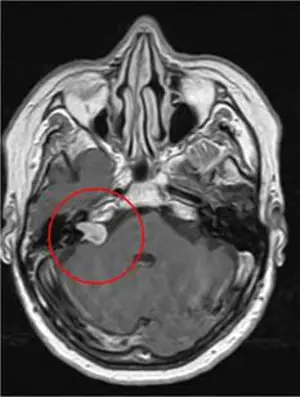

МРТ-изображение с двумя метастазами рака легкого в головной мозг

Оба метастаза были удалены за один сеанс, длительностью 1 час. На снимке результат контрольного обследования через 4 месяца после лечения. Обе опухоли были удалены, после лечения пациент в тот же день вернулся к работе